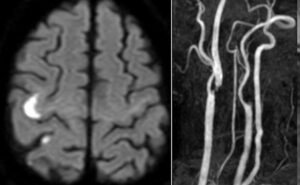

最近はCASばかりで年一回ほどになっていますが、久しぶりにCEAを行いました。東野先生に執刀してもらいました。やはりブランクがあると、ダメですね。分岐部が低すぎるのもありいつもより総頸動脈の露出が足りませんでした。また珍しいことに遮断をして切開すると血液が出てきました。手術を見学していた大岩先生が、ascending pharyngeal arteryが分岐部の裏から出ていることを指摘され、完全遮断できました。プラークの摘出は容易でしたが、最後また総頸動脈の一番近位部からリークがあり、これも一針追加しました。手術は色々あるものですが、東野先生を見ているとCEAは任せられそうでした。若手の手術がとても上手になってきています。患者さんも元気で良かったです。

久しぶりにCEAをやりました